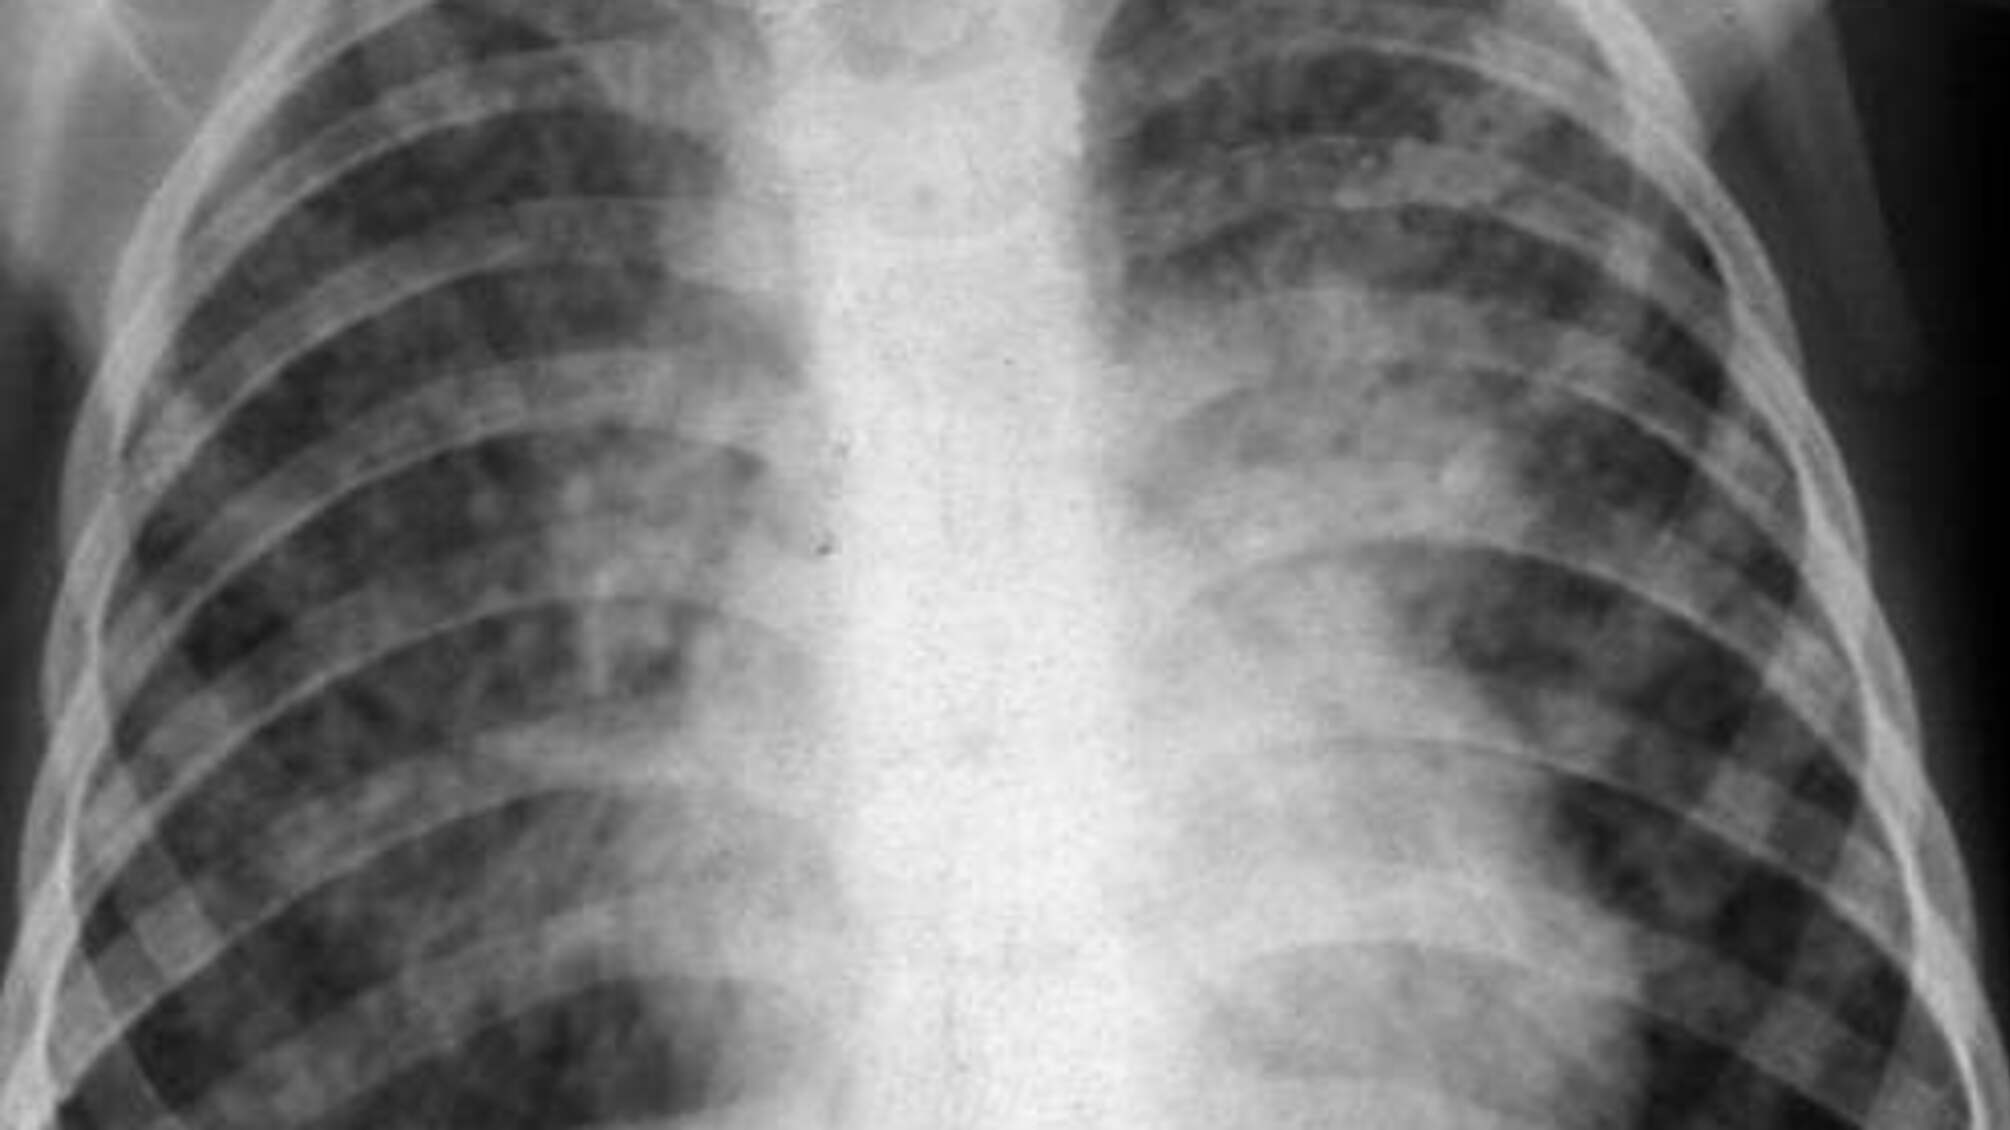

Медики повідомляють, що серед хворих переважають люди працездатного віку, а 80 відсотків усіх випадків – це туберкульоз легенів. Якісне лікування хворим на окупованих територіях Луганщини забезпечити не можливо – лікувати нікому і нічим.